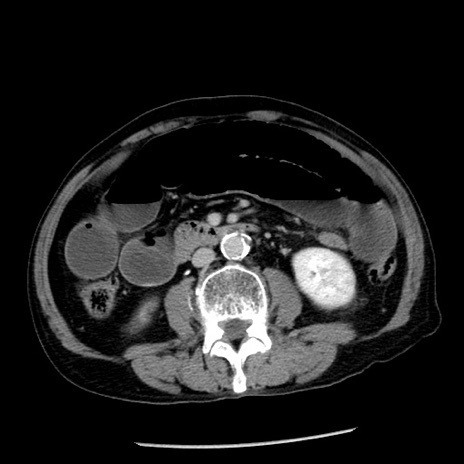

症例26(横断像)

【症例】80歳代男性

【主訴】嘔吐

【現病歴】昨晩2回嘔吐あり、今朝になっても嘔吐あり。来院。

【既往歴】胃潰瘍

【身体所見】意識清明、BT 37.6℃、BP 166/95mmHg、HR 100bpm、SpO2 97%、腹部:平坦・軟、腸蠕動音聴取良好、圧痛なし。

【データ】WBC 21900、CRP 1.46